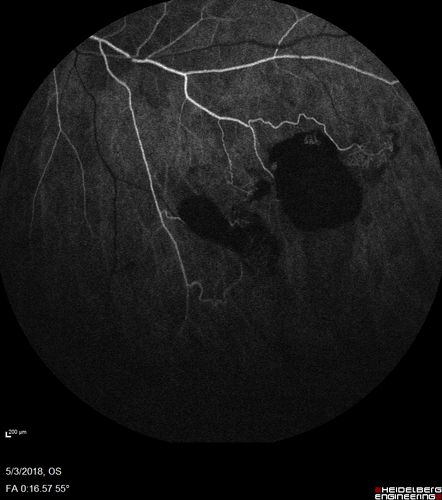

Coats' Disease -51 year old asymptomatic male

20/20 vision - had laser to non-perfusion because of proliferation.